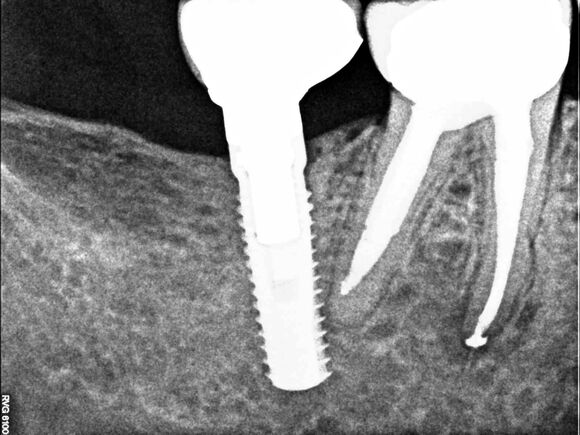

Beispiel 2: Vorher

Ausgedehnte Entzündung neben einem Implantat, bei diesem Überweisungsfall.

Beispiel 2: Nachher

Nur 6 Monate später ist die Entzündung fast vollständig zurückgegangen - Zahn und Implantat sind gerettet.